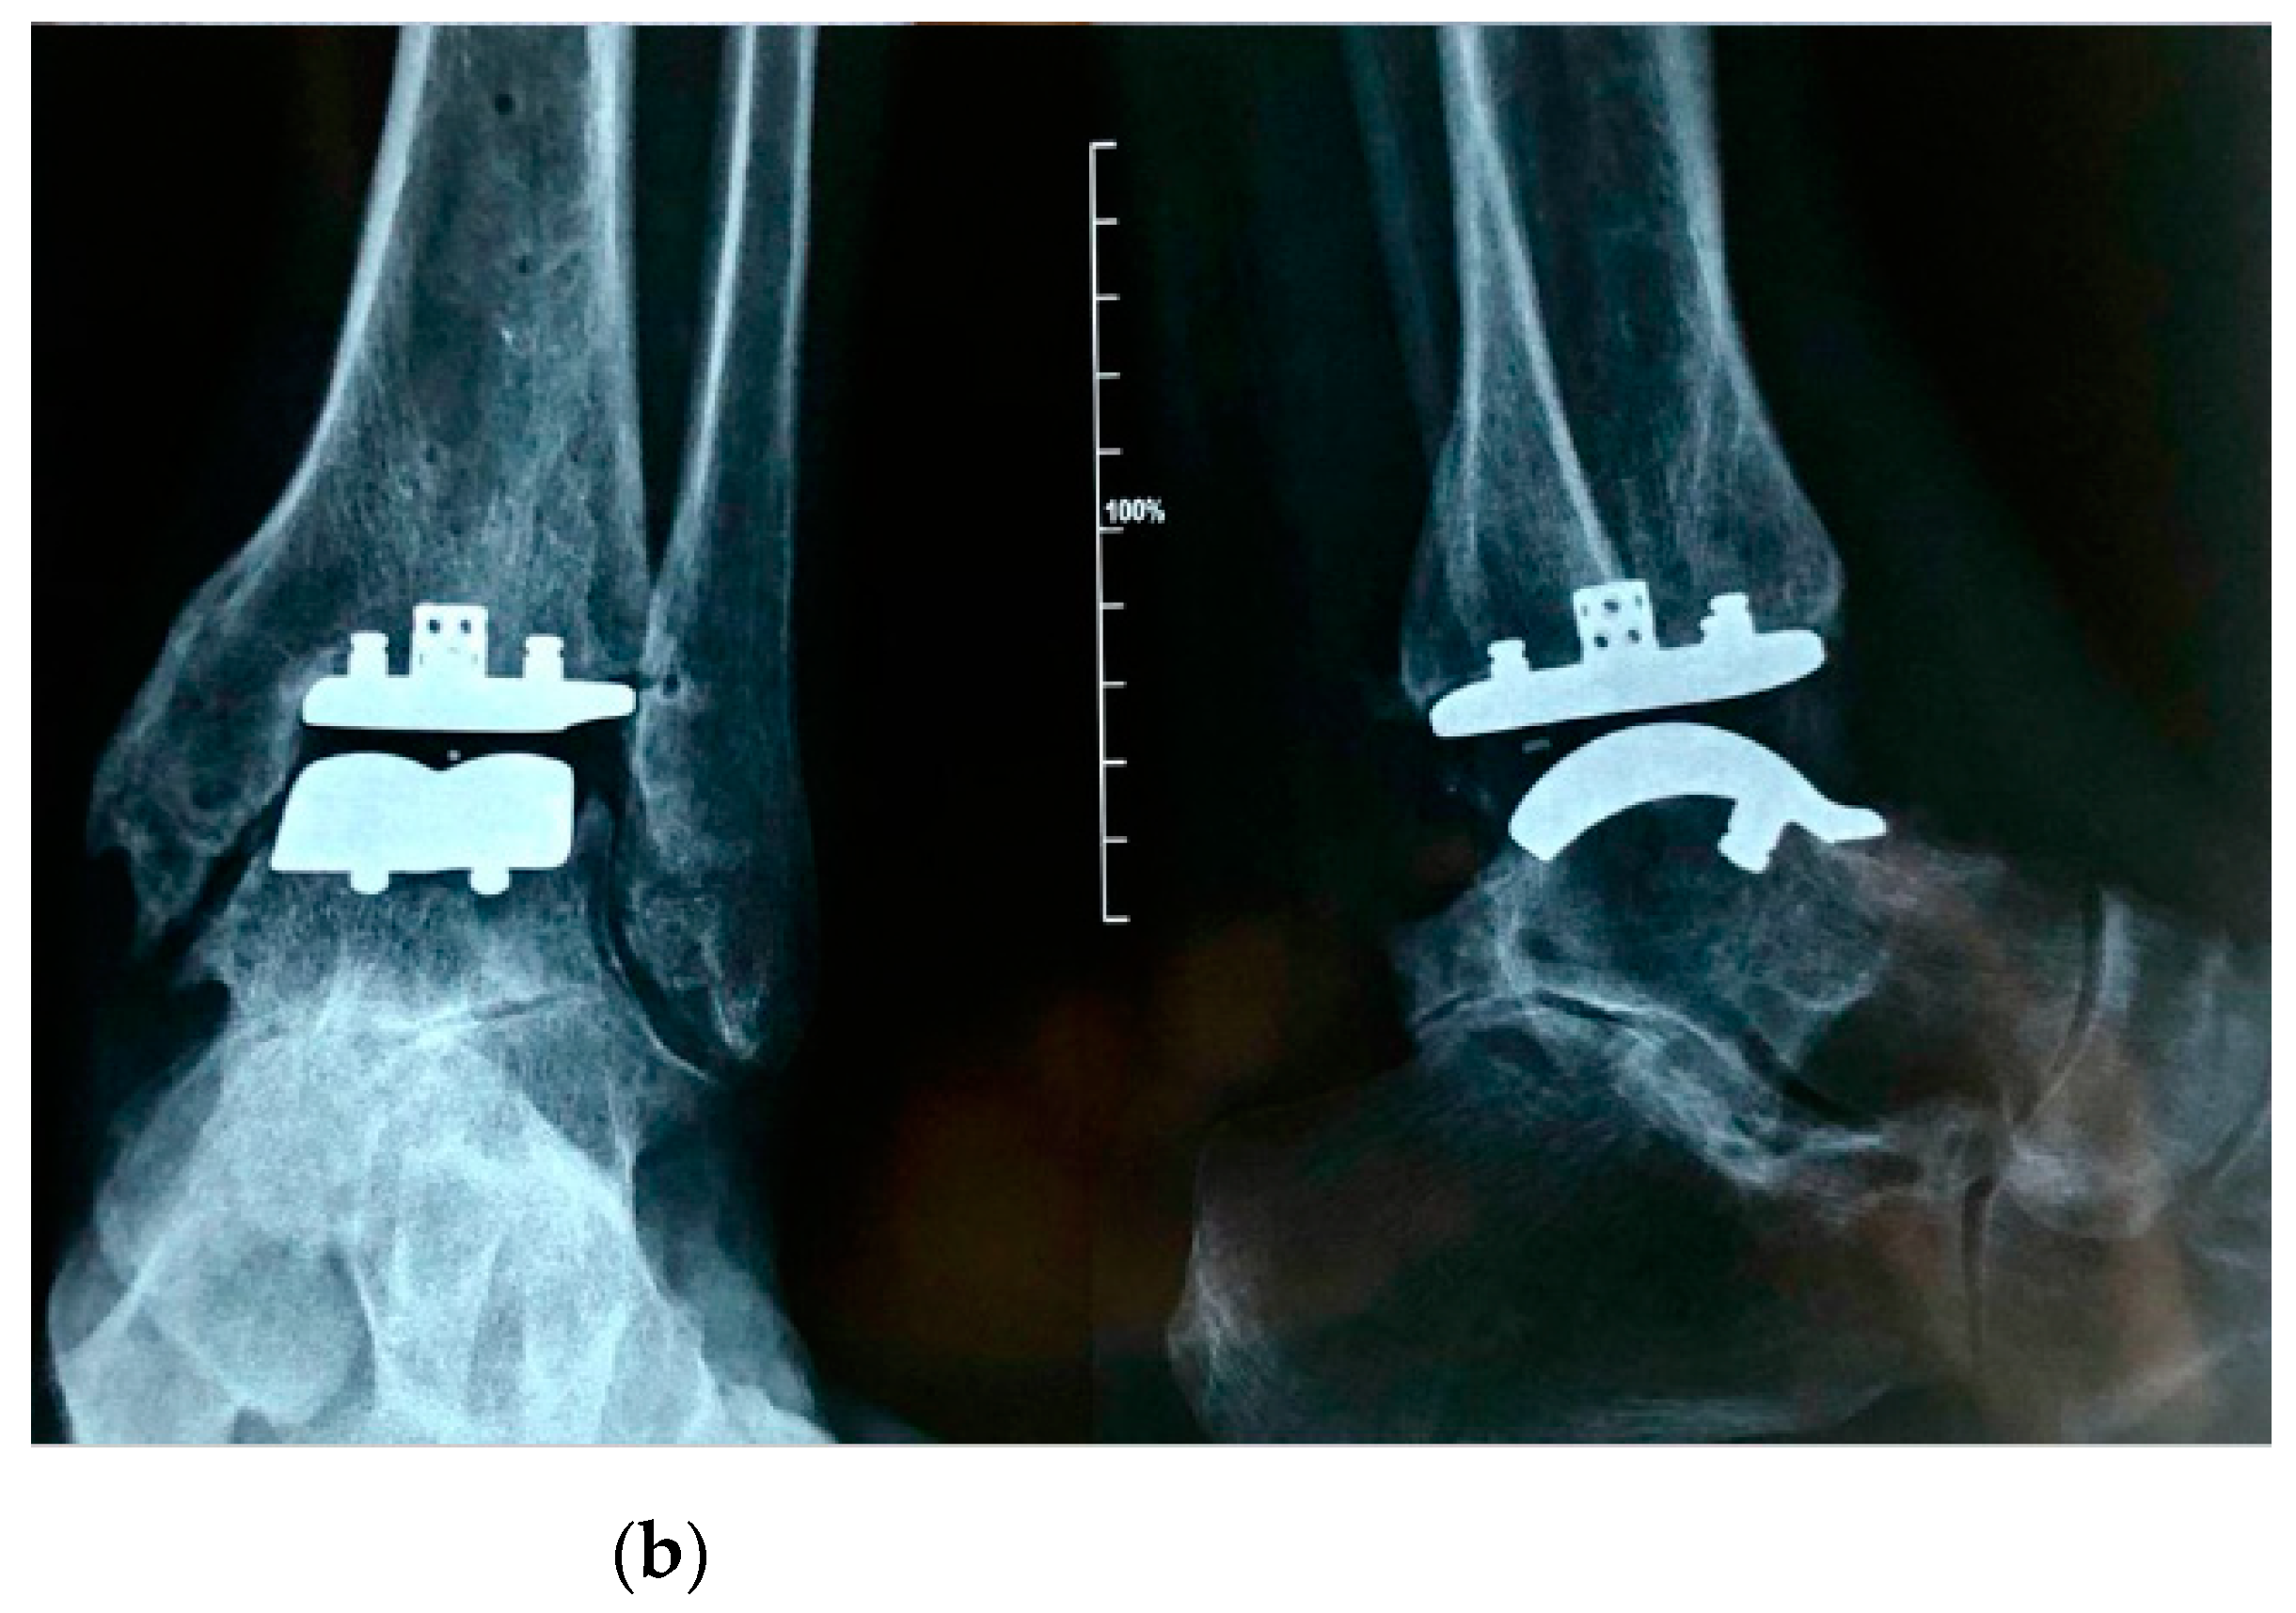

Figure 1.

Pre-operative radiographic image in anteroposterior and lateral view (on the left and on the right, respectively) of an arthritic ankle joint, with a slight articular varus deformity (a) and post-operative radiographic results (b).